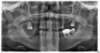

CAS DE RÉHABILITATION COMPLÈTE EN MISE EN CHARGE IMMÉDIATE

Avant

Apres

Patient apres pose de bridge provisoire immédiat